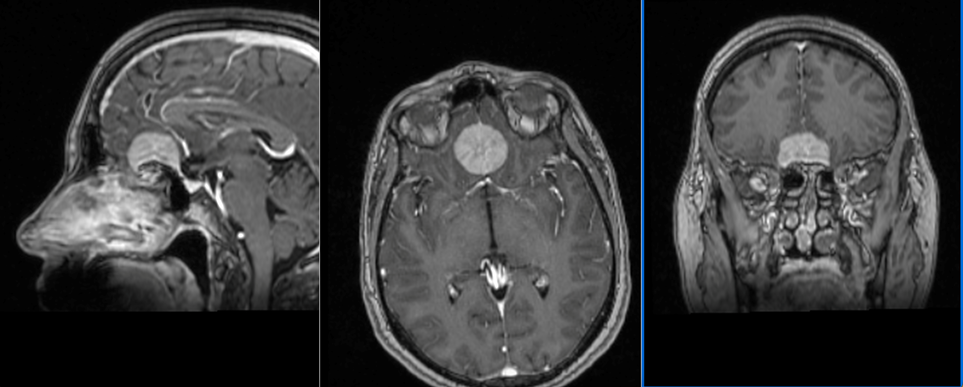

Meduloblastomul la adult Meduloblastomul este o tumoră malignă a sistemului nervos central, cunoscută mai ales ca fiind tipică copilăriei....